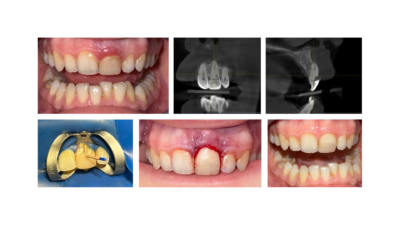

პაციენტი: 16 წლის

მდგომარეობა:

- არასწორად ჩატარებული რესტავრაცია

- არასწორად ჩატარებული ოპერაცია-ღრძილის მოკვეთა ანუ გინგივექტომია (2-ჯერ)

- პაციენტს სურდა კბილის გვირგვინის ესთეტიკურად დაგრძელება

მკურნალობის გეგმა:

- 3D კ. ტომოგრაფიული კვლევა (გამოვლინდა კბილის ფესვის ვესტიბულური, ღრმა დაზიანება)

- პაროდონტოლოგიური მკურნალობა

- კლინიკურად ღრძილის გამოჯანმრთელების შემდეგ დაიგეგმა 2.1 კბილის ესთეტიკური დაგრძელება პლასტიკური ქირურგიული გზით

- კბილის ფესვის დაბჟენა ვესტიბულური მიდგომით

კომპოზიტით დაფარვა მოხდა მხოლოდ ოპერაციულ ზონაზე, ქსოვილების მინიმალური ინვაზიური პრეპარირების პრინციპით (სრულად შენარჩუნდა სასისკენა ქსოვილი), კლინიკური გამოჯანმრთელება ასახულია ფოტოზე 2 თვის შემდეგ და ამ ეტაპისთვის იგეგმება 2.1 კბილის გვირგვინის მხატვრული რესტავრაცია.

ქირურგი/პაროდონტოლოგი: სოფო დიასამიძე

კბილის ენდოდონტიური მკურნალობა შეასრულა თერაპევტმა თამუნა დუნდუამ